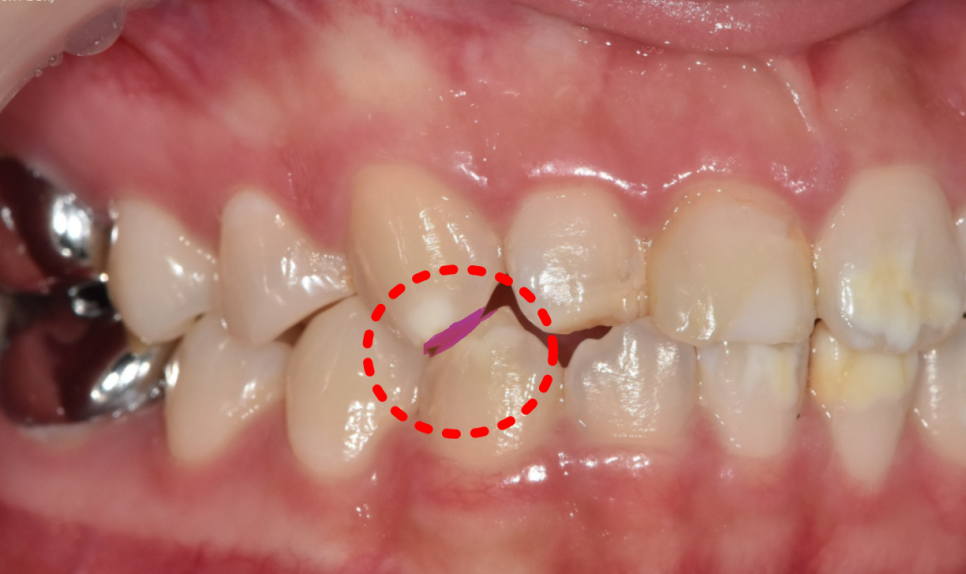

특히 왼쪽 송곳니는 탈회가 진행돼서 초기 충치로 변하고 있는 상태였어요.

충치가 진행된 모습

양측 송곳니를 보니,

반대편 치아와 물리는 부분이 너무 긴밀합니다.

쉽게 말하면, 위 치아가 아래 치아를 덮지 않고 씹는 면 끝과 끝이 물리더라고요.

이런 경우 라미네이트를 하면

깨질 가능성이 높습니다.